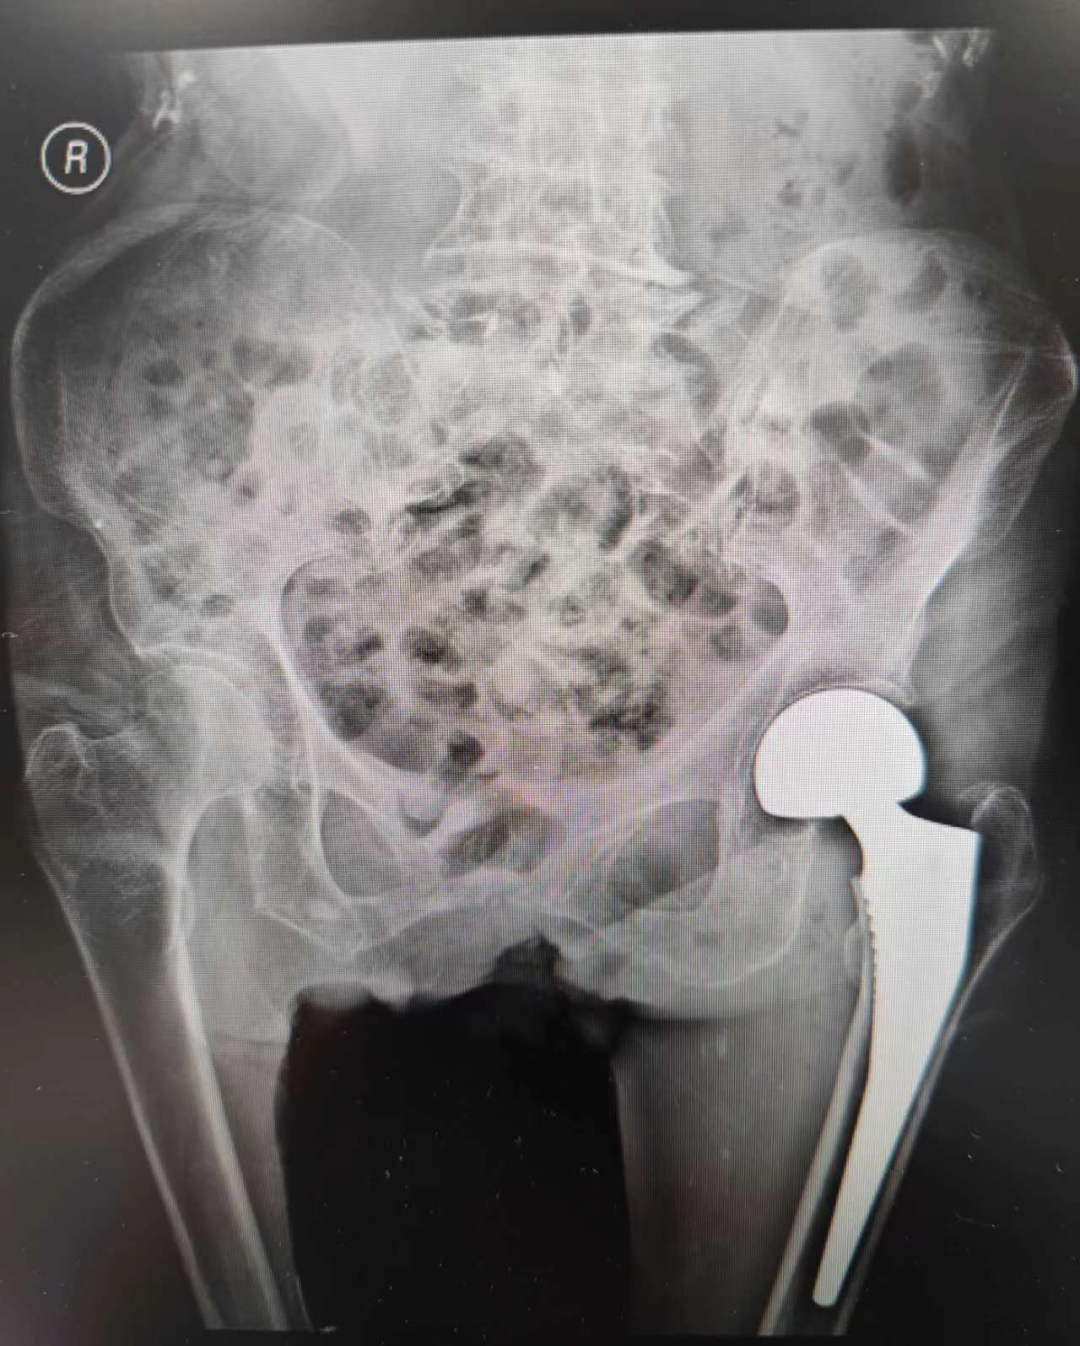

术前DR片显示左股骨颈骨折

术后DR片